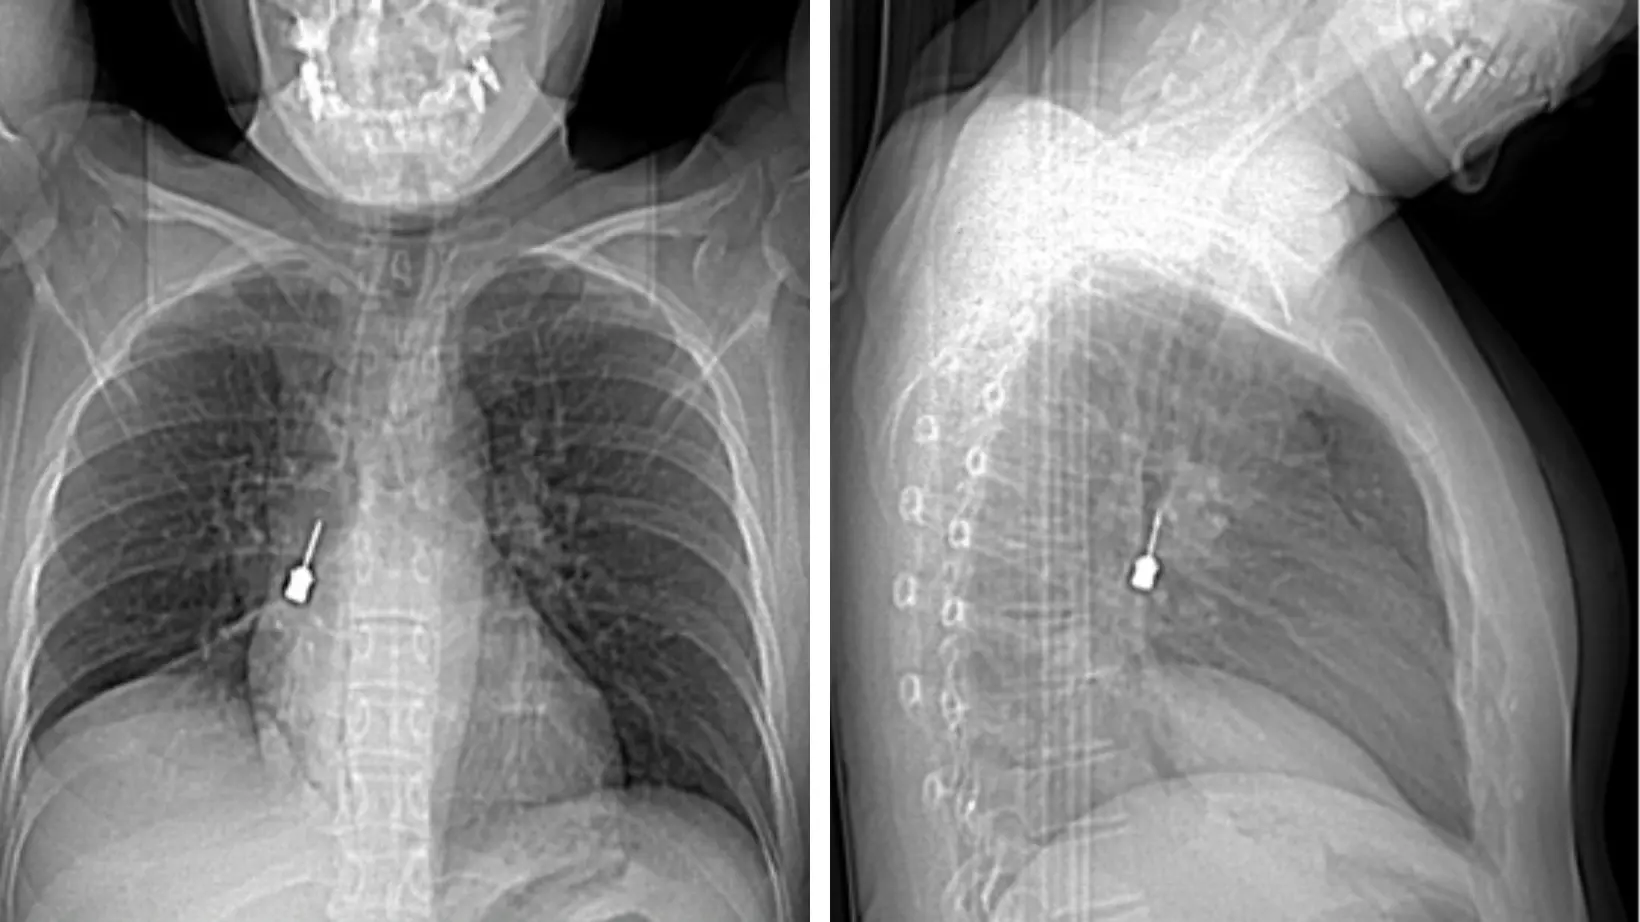

La paziente è giunta al Pronto Soccorso del Gom esibendo un esame di diagnostica per immagini (Tomografia Computerizzata) eseguito a causa di una tosse persistente e di un forte dolore a livello toracico. La TC mostrava la presenza di un corpo estraneo metallico pericolosamente incastrato nel bronco lobare inferiore del polmone destro e un concomitante pneumomediastino, ossia la presenza di aria nello spazio compreso fra i due polmoni.